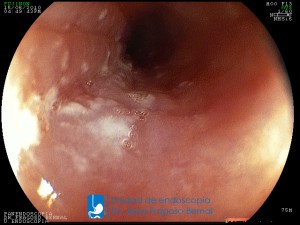

La Unidad de Endoscopía fue creada en 2002 por el Dr. Jesús Fragoso Bernal, es pionera en el estado por la utilización de la tecnología más avanzada, que nos permite ofrecer servicios integrales de diagnóstico y tratamiento para las enfermedades del aparato digestivo.

"La Unidad de Endoscopía se ha caracterizado por un progreso continuo desde su inicio marcando la pauta en los procedimientos endoscópicos en el estado de Tlaxcala y estando siempre a la vanguardia tecnológica."

Dr. Jesús Fragoso Bernal